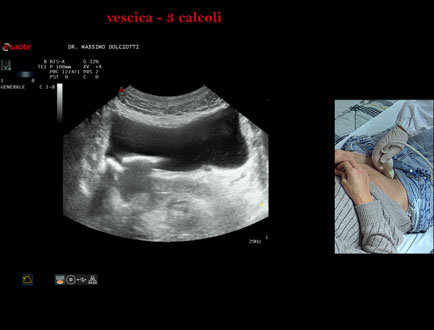

Data inserimento: 21/10/2025

Ecografia del: 15/10/2025

Strumento: Esaote MyLab Eight

Sonda: Convex Multifrequenza 1-8 MHz

Età Paziente: F 45 anni

Motivazione dell'esame: da alcuni mesi, disuria ed infezioni urinarie recidivanti.

Commento all'esame: le immagini ed il video documentano 3 immagini iperecogene, con cono d'ombra posteriore, da ricondurre a litiasi multipla della vescica.

Conclusioni: 3 calcoli della vescica (3 bladder stones).

Presentazione: Dr. Massimo Dolciotti - Ancona

Elaborazione digitale: Andrea Dini - Ancona